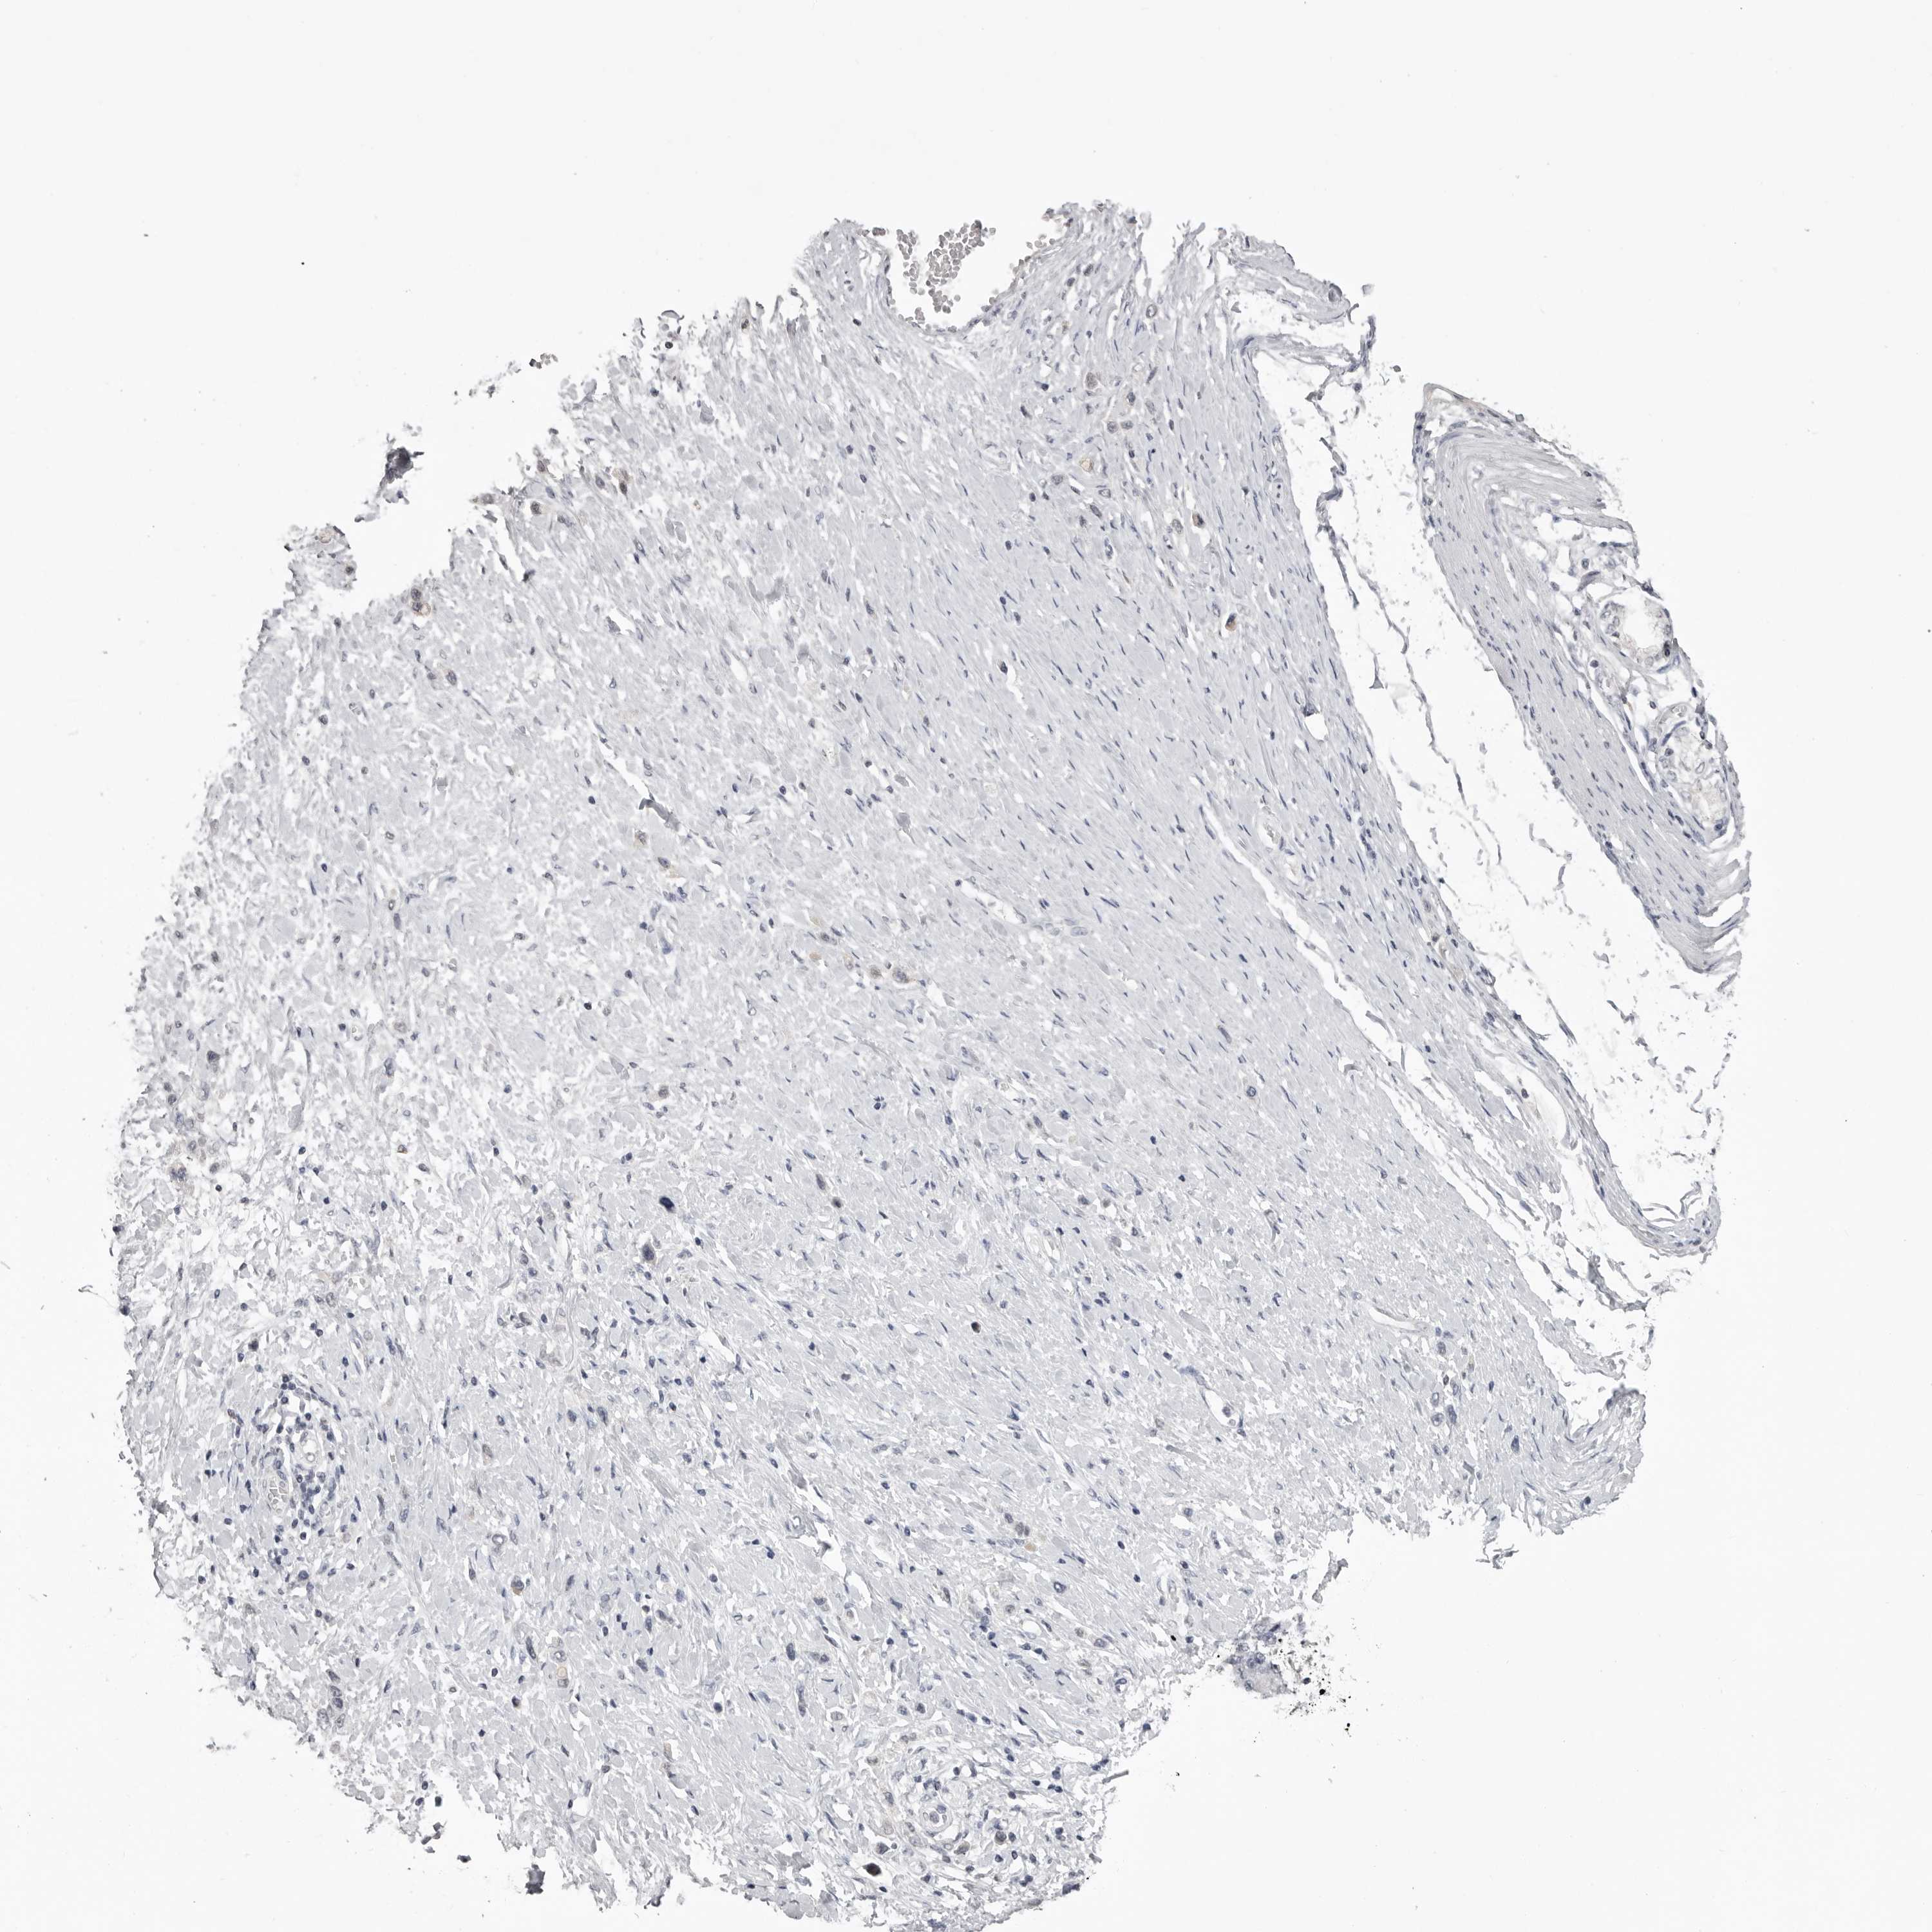

STOMACH CANCER - Protein expressioni

A mouse-over function shows sample information and annotation data. Click on an image to view it in a full screen mode. Samples can be filtered based on level of antibody staining by selecting one or several of the following categories: high, medium, low and not detected. The assay and annotation is described here.

Antibody stainingi

Antibody staining in the annotated cell types in the current human tissue is reported as not detected, low, medium, or high, based on conventional immunohistochemistry profiling in selected tissues. This score is based on the combination of the staining intensity and fraction of stained cells.

Each image is clickable and will lead to virtual microscopy that enables deeper exploration of all samples and also displays staining intensity scores, fraction scores and subcellular localization as well as patient and tissue information for each sample.

Antibody HPA028059

Staining

High

Medium

Low

Not detected

Intensity

Strong

Moderate

Weak

Negative

Quantity

>75%

75%-25%

<25%

None

Location

Nuclear

Cytoplasmic/membranous

Cytoplasmic/membranous,nuclear

Adenocarcinoma, NOS